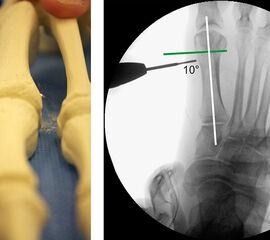

Abbildung 1

• Korrekturpotential größer als beim offenen Chevron, da die Gelenkkapsel als stabilisierendes Element erhalten bleibt und über eine trikortikale Osteosynthese mit zwei kanülierten Schrauben eine Verschiebung bis ca. 80% des Metatarsaledurchmessers möglich ist (Abb. 1).